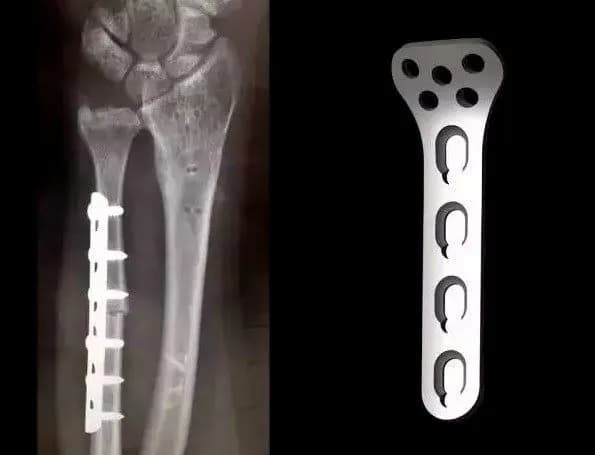

Płytki tytanowe to elementy medyczne, które odgrywają kluczową rolę w chirurgii ortopedycznej. Wykonane z tytanu, materiału znanego ze swojej lekkości oraz wytrzymałości, są stosowane do stabilizacji kości po urazach lub operacjach. Dzięki swojej biokompatybilności, tytan nie wywołuje reakcji alergicznych ani odrzucenia przez organizm, co czyni go idealnym materiałem do zastosowań medycznych.

Płytki tytanowe są wykorzystywane w różnych procedurach chirurgicznych, takich jak naprawa złamań czy rekonstrukcja stawów. Ich główną funkcją jest wspieranie procesu gojenia poprzez stabilizację uszkodzonych kości. Tytanowe płytki są często stosowane w połączeniu z innymi implantami, aby zapewnić maksymalną efektywność leczenia i przyspieszyć powrót pacjenta do zdrowia.

Płytki tytanowe pełnią istotną funkcję w chirurgii ortopedycznej, ponieważ zapewniają niezbędne wsparcie dla kości w trakcie procesu gojenia. Dzięki swojej wytrzymałości i elastyczności, umożliwiają one stabilizację złamań oraz wspomagają regenerację tkanek. W przypadku poważnych urazów, takich jak złamania wieloodłamowe, płytki tytanowe są szczególnie ważne, ponieważ pomagają utrzymać prawidłowe ułożenie kości, co jest kluczowe dla prawidłowego gojenia się.

Płytki tytanowe są szeroko stosowane w różnych procedurach chirurgicznych, szczególnie w przypadku złamań oraz rekonstrukcji stawów. W przypadku złamań, płytki te stabilizują kości, co jest kluczowe dla ich prawidłowego gojenia. Na przykład, w przypadku złamania kości udowej, lekarze mogą zastosować płytkę tytanową, aby utrzymać fragmenty kości w odpowiedniej pozycji, co przyspiesza proces regeneracji.